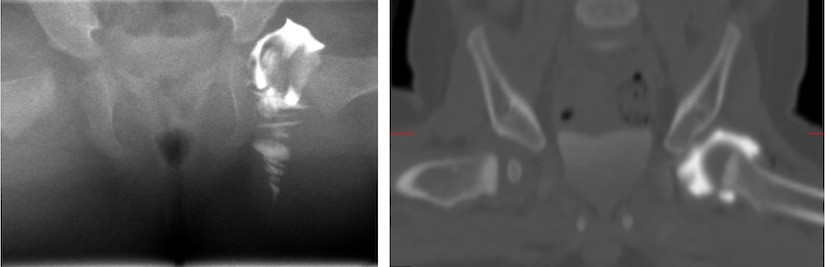

Links: CT-scan van het bekken van een baby van 8 maanden. Dwarsdoorsnede door het heupgewricht. De heupkoppen zijn gemarkeerd met witte pijlen. De linkerheupkop is naar achter (rugzijde) geluxeerd. Dit is op een röntgenfoto niet goed te zien.

Rechts: CT-scan van het bekken van dezelfde baby als figuur 7, 1 maand na repositie. De linkerheupkop staat goed in de kom..

Bij kinderen met heupluxatie kan een CT-scan worden gebruikt om te controleren of de heupkop goed in de heupkom staat als het niet lukt om dit op een andere manier te bekijken.

Bij volwassenen wordt een CT-scan vaak gebruikt om breuken rond het heupgewricht op te sporen na een ongeval.